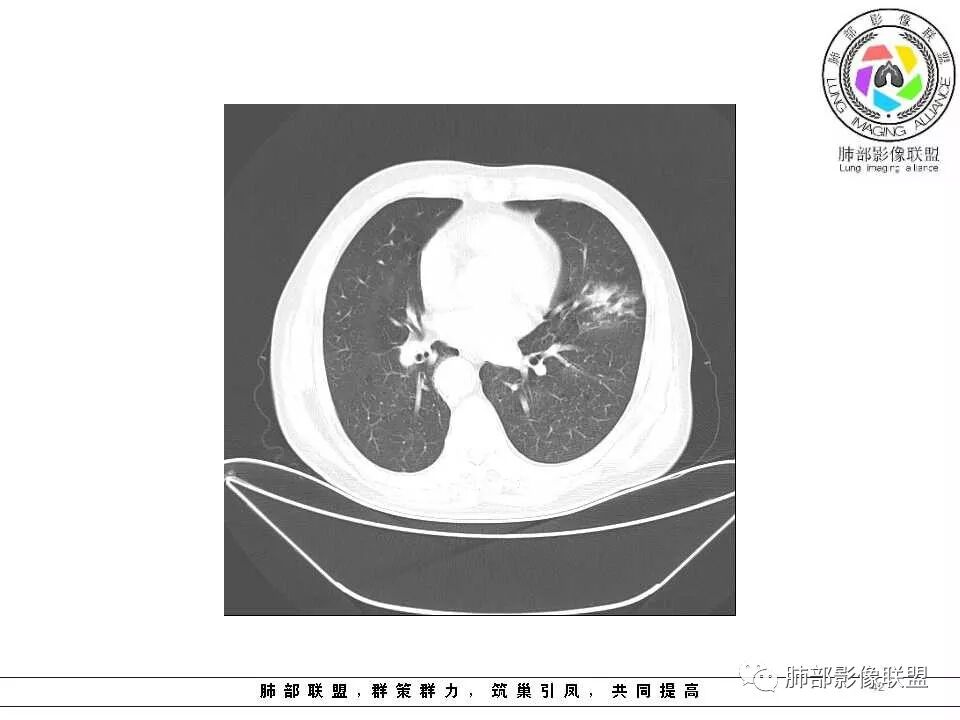

老年男性,肺气肿基础。约一年时间出现左肺上叶舌段支气管近端结节影,远端斑片样阴影,边缘模糊。考虑近端恶性占位,远端有阻塞性炎症。

老年男性,有咳血病史,左肺上叶舌段一年时间出现新发类圆形小结节,感觉在支气管内,部分凸出气管外,没有mpr不好说,远端肺野斑片模糊影,考虑阻塞性炎症,纵隔无明显肿大淋巴结,小细胞代排,按照发展速度,类癌低度恶性,应该发展缓慢,一年病史,代排,首先考虑鳞癌并阻塞性炎症

肺气肿背景,2016年左肺上叶上舌段见微结节,2017年5月左肺结节增大,密度均匀,边缘光滑锐利,与邻近血管关系密切,血管贴壁走行,外侧见尖状突起,下舌段片状影,沿着支气管走行,内有粘液栓,考虑鳞癌,鉴别小细胞肺癌。

支气管来源恶性病变,继发远端阻塞性炎症,鳞癌,类癌

肺气肿背景,2016年左肺上叶上舌段见微结节,一年后左肺结节增大,密度均匀,边缘光滑、膨隆,似见小分叶,下舌段片状影,沿着支气管走行,内,老年患者,咯血1月。考虑恶性病变并阻塞性肺炎,鳞癌?注意鉴别结核。

左肺上叶舌段支气管管壁略增厚 间隔一年 管壁增厚明显 向腔外突出形成结节 管腔闭塞 远端片状及斑片影 纵隔淋巴结增大 肺气肿背景 考虑鳞癌伴阻塞性炎症可能

老年男性,咯血1月,肺气肿背景,16年左肺上叶舌段结节,左肺门疑似淋巴结肿大,呈结节感。17年左肺上叶舌段见沿支气管走行分布结节 远端阻塞性肺炎,左肺门淋巴结肿大明显,首先考虑恶性病变,鳞癌?类癌?

老年男性,肺气肿背景,左肺上叶舌段一年前小结节后长大,实性,与邻近气管关系密切,远端有少许小片状炎症类小结节状,左肺门淋巴结肿大,首先考虑恶性,鳞癌可能性大,代排小细胞癌。病灶下方斑片状影,考虑炎症。

老年男性,肺气肿背景,对比前片,左肺上叶舌段结节较前进展,周围有斑片状条状密度增高影,左肺门淋巴结肿大,有咯血史抗炎后效果不佳,目测增强强化不好判断,考虑肺癌并阻塞性肺炎可能,鉴别炎症性肺癌,真菌类肺炎,肺脓肿,肺结核,建议完善肿瘤标志物,结核相关检查,病原体检查。

老年男性,咯血一个月,有慢支病史。左肺上叶舌段可见一类圆形结节影,边缘光滑,远端有片条状影,一年前胸ct基本正常。感觉还是考虑肺癌合并阻塞性炎症。鳞癌还是小细胞?

老年男性,咯血1月,肺气肿背景,左肺上叶舌段见沿支气管走行分布结节,呈葫芦样改变,左肺门淋巴结肿大明显,首先考虑恶性病变,小细胞癌可能

常规腔内病灶引起远端炎症:

1、肿瘤,良性、恶性?短时间出来——恶性

就目前的资料:我支持恶性肿瘤,待排异物

晨读结果:鳞状细胞癌